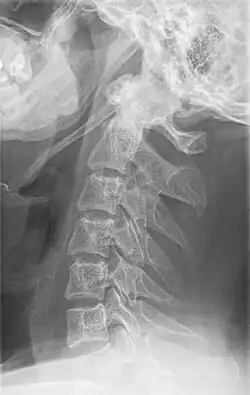

Radiograph, lateral view showing elongated stylohyoid process and stylohyoid ligament ossification -

Radiograph, lateral view showing joint-like formation in ossified stylohyoid ligament -

Diagnosis is suspected when a patient presents with the symptoms of the classic form of "Eagle syndrome" e.g. unilateral neck pain, sore throat or tinnitus. Sometimes the tip of the styloid process is palpable in the back of the throat. The diagnosis of the vascular type is more difficult and requires an expert opinion. One should have a high level of suspicion when neurological symptoms occur upon head rotation. Symptoms tend to be worsened on bimanual palpation of the styloid through the tonsillar bed. They may be relieved by infiltration of lidocaine into the tonsillar bed. Because of the proximity of several large vascular structures in this area this procedure should not be considered to be risk free.

Imaging is important and is diagnostic. Visualizing the styloid process on a CT scan with 3D reconstruction is the suggested imaging technique.[13] The enlarged styloid may be visible on an orthopantogram or a lateral soft tissue X ray of the neck.